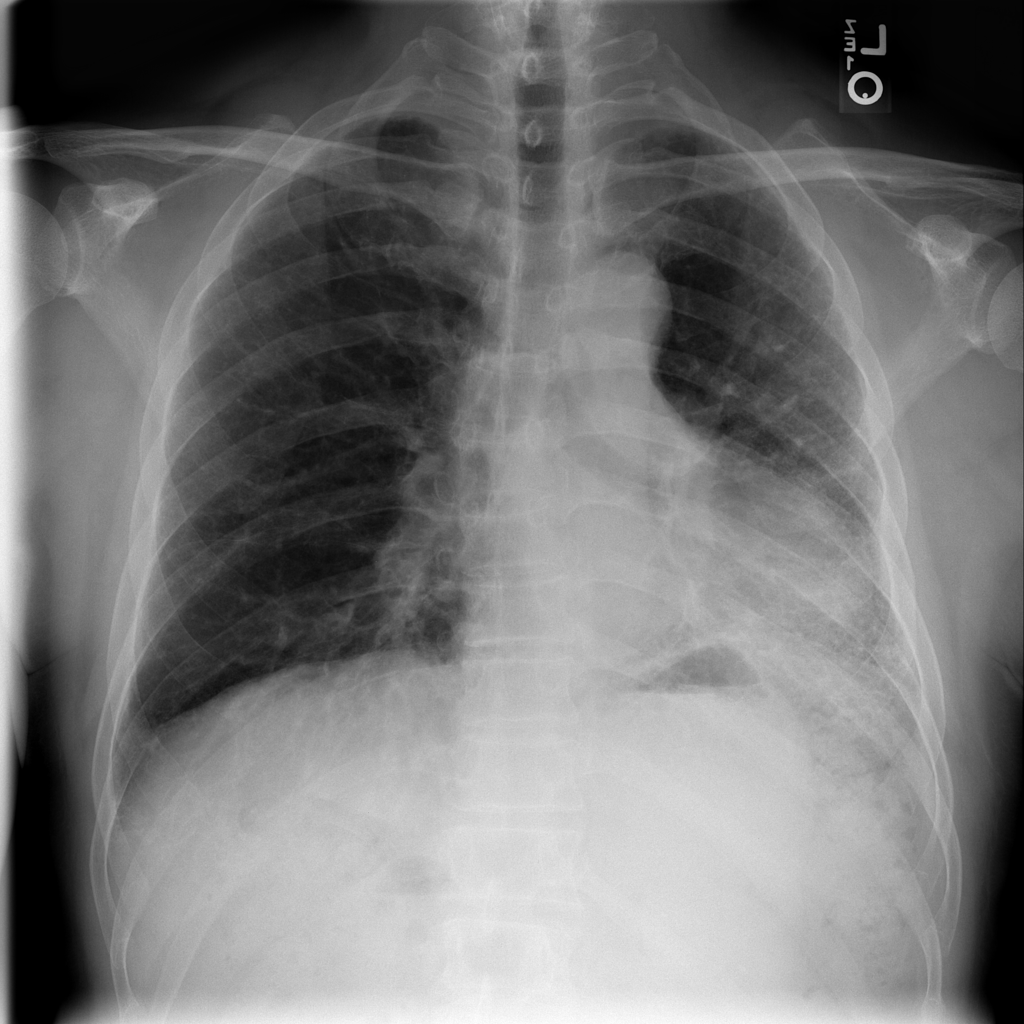

PAT-C77C · IMG-003Fibrosis

PAT-C77C · IMG-003

PA